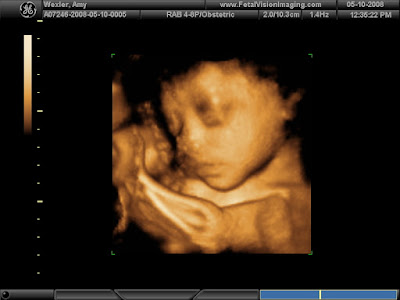

Does He Look Like Me?

Saturday, our families joined us for a 4D ultrasound in Langhorne. It's something you can do for fun, there is nothing clinical about it. It's about a half an hour session. The room is big enough for about 10 people and they project the images on the wall. We were hoping the baby would cooperate. We know some people who did this recently and couldn't see anything as the babies were facing the wrong way or had limbs in front of their faces. Our baby did pretty well. He slept through most of it but you can see his eyes open a little in one picture. His feet, hand and umbilical cord kept moving in front of his face but tapping on the belly seemed to help. I'll put up some baby pictures of me and Amy so you can compare.